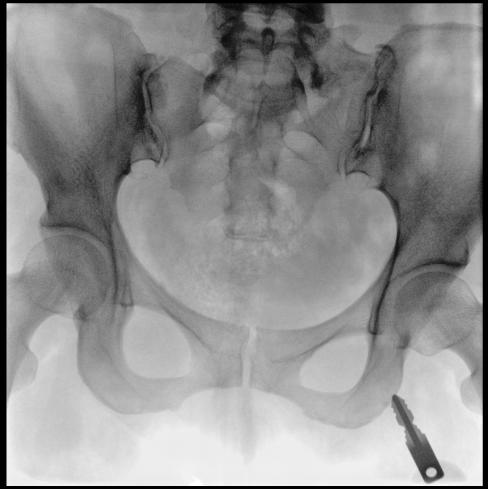

臨床應(yīng)用廣泛,適用于關(guān)節(jié)手術(shù)、創(chuàng)傷手術(shù)、脊柱手術(shù)、疼痛治療等。

●屏幕內(nèi)置DICOM醫(yī)學(xué)曲線,幫助辨認(rèn)細(xì)微組織的密度變化。

●27英寸大尺寸顯示器,更大視野,方便觀察微小結(jié)構(gòu)。

●一屏雙顯,可同時觀察正側(cè)位圖像,便于對比觀察。